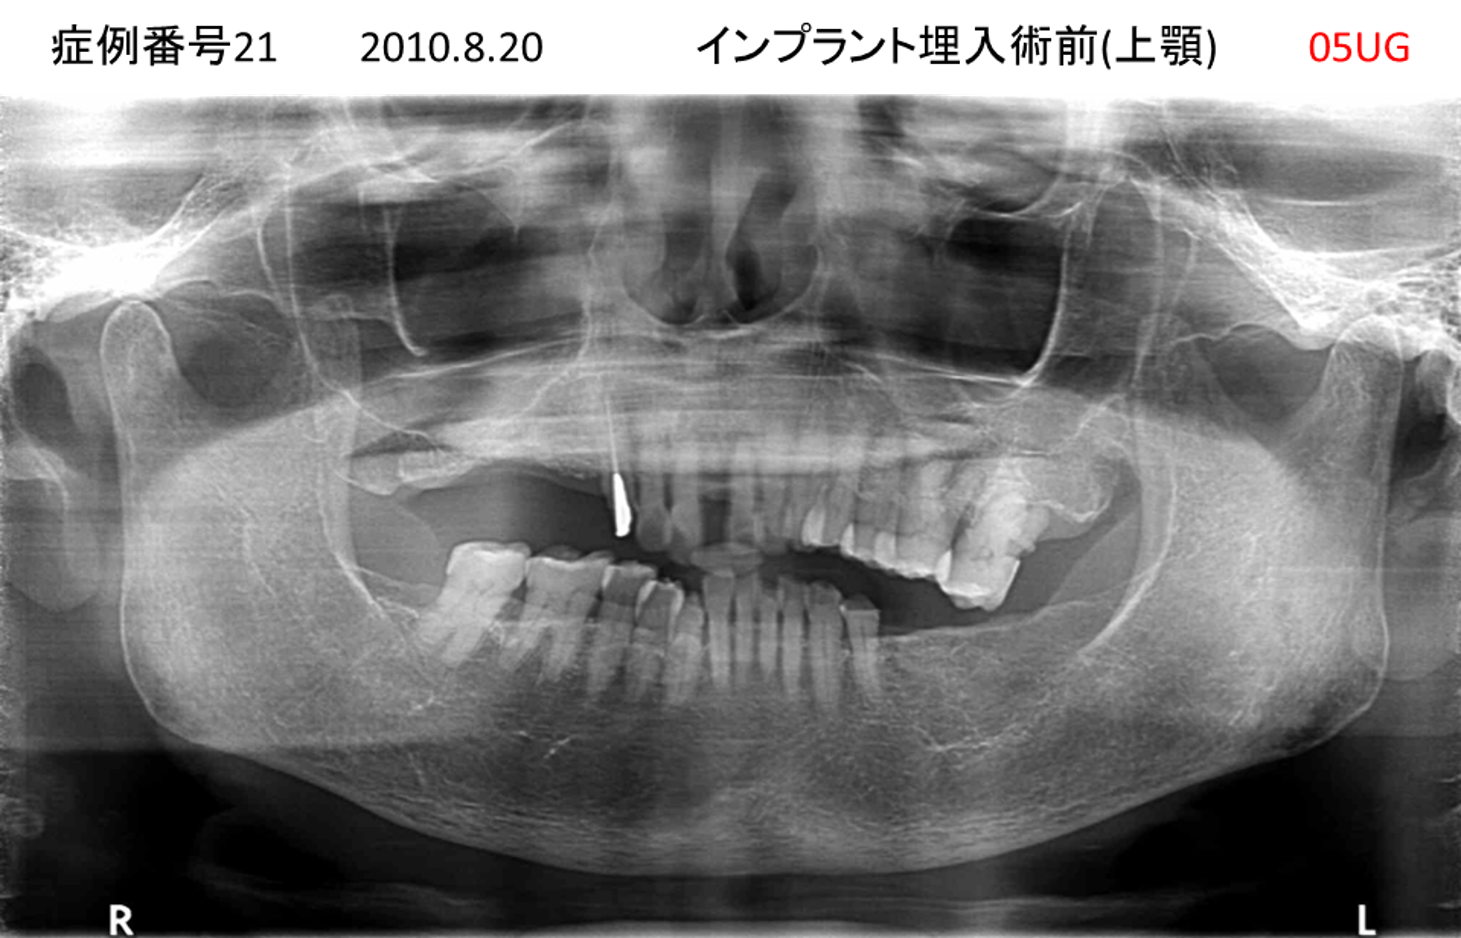

全く噛めない患者様のインプラント症例

| 治療名称 |

インプラントオーバーデンチャー |

| 治療費用 |

520万円+税 |

| 治療期間 |

6か月 |

| 患者さんの症状(主訴) |

全く噛めない。何とかしてほしい |

| 治療内容 |

サイナスリフト、インプラント、義歯作製(ロケーター) |

| 治療結果 |

好きなものが食べられるようになった。見栄えがとても良くなった。 |

| 治療の注意点(リスク/副作用) |

義歯が壊れた場合、インプラントが壊れた場合は再治療が必要 |